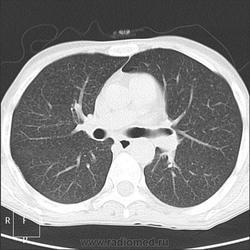

Прозрачность обеих легких равномерно неинтенсивно снижена за счет наличия множественных, плохо дифференцируемых мелкоочаговых теней, сливающихся между собой и расположенных главным образом во внутренних отделах легких, ближе к корням легких, образуя картину «бабочки». Сосудистый рисунок диффузно усилен, в виде радиальных извитых теней за счет перибронхиальной и периваскулярной инфильтрации. Линейные тени пластинчатых ателектазов. Корни легких малоструктурны. Органы средостения не смещены. Сердечная тень не увеличена."

Я не вижу "Бабочку", а Вы?

Из-за почечной недостаточности контрастирования не будет. Такая картина в легких мне впервые попадается. Есть несколько вариантов, но очень хочется услышать мнения коллег! Какие будут мысли?

В легких - рентгенограмму я описала как усиление за счет интерстициального компонента. Корень кажется обрубленным: из-за асцита высоко стоит диафрагма, нижние отделы легких поджаты. Пневмосклероза я не вижу. А по КТ не знаю, как интерпретировать: интерстициальный отек, токсический васкулит?

В легких обычное сдавление нижних отделов за счет высокого давления в брюшной полости.

Тогда, учитывая всё вышесказанное, вероятно интерстициальный отёк ( гипопротеинемия, почечная недостаточность, токсическое поражение...)

Интерстициальный отек легких. Хронический калькулезный панкреатит. Киста хвоста поджелудочной железы, без биопсии уверенно раковое перерождение не исключить. Киста сальниковой сумки /вероятно тоже панкреатического генеза/. Жировой гепатоз печени с портальным циррозом /биопсия/. Камень устья? пузырного протока. Геморрагические кисты почек??? Асцит.

Парочка моих шаблонов, наверное первый соответствует настоящему состояниюПрозрачность обеих легких равномерно неинтенсивно снижена за счет наличия множественных, плохо дифференцируемых мелкоочаговых теней, сливающихся между собой и расположенных главным образом во внутренних отделах легких, ближе к корням легких, образуя картину «бабочки». Сосудистый рисунок диффузно усилен, в виде радиальных извитых теней за счет перибронхиальной и периваскулярной инфильтрации. Линейные тени пластинчатых ателектазов. Корни легких малоструктурны. Органы средостения не смещены. Сердечная тень не увеличена.

Прозрачность обеих легких неравномерно, преимущественно в нижних отделах, неинтенсивно снижена за счет наличия множественных, плохо дифференцируемых крупноочаговых теней, сливающихся между собой и расположенных главным образом во внутренних отделах легких, ближе к корням легких, образуя картину «бабочки». В прикорневых и паравертебральных отделах значительное усиление сосудистого рисунка, размытого грубопетлистого, обусловлено венозным полнокровием. Тени венозных сосудов определяются, как поперечно расположенные полосы с нерезкими контурами, преимущественно в нижних отделах. Определяются горизонтальные линии Керли вследствие интерстициального отека междольковых перегородок Корни легких расширены малоструктурны. Органы средостения не смещены. Сердечная тень увеличена в поперечнике, талия сглажена, аорта уплотнена, умеренно развернута

Я не вижу "Бабочку", а Вы?